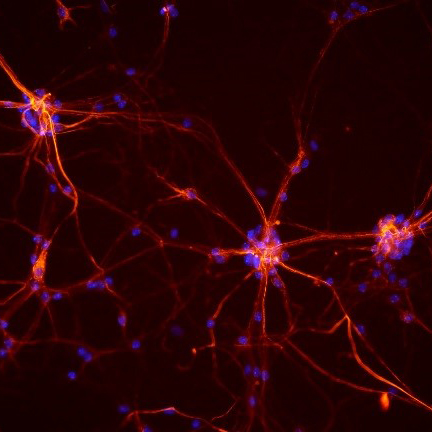

Proximity to nearby muscle cells may make prostate cancer cells more likely to invade nearby tissues and spread to other organs, according to an early study by researchers at the National Institutes of Health. The presence of muscle cells appears to make cancer cells more likely to fuse two or more cancer cells into a single cell, thereby increasing their invasiveness and ability to spread.